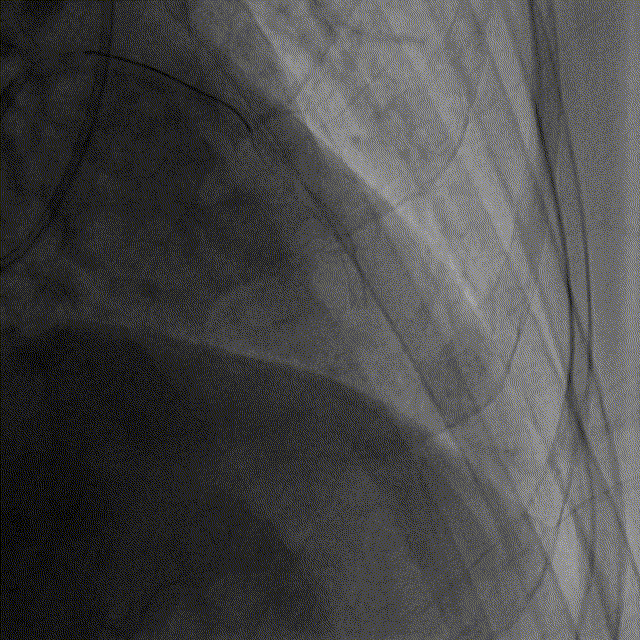

RCA植入支架后

面对管腔严重狭窄且病变弥漫的LAD病变,将成像导管顺利送至病变远端才能进行准确地评估。NOPURGE®成像导管的通过外径仅为2.52F,导管头端直径较小,头端距镜头更近,可以送入冠脉更远的位置,亲水涂层设计大大提升了导管的通过性,一体化无焊点结构则进一步保障了导管在迂曲病变中的通过性,在临床实际应用中具有很大优势。随后钱菊英教授再次使用微创阿格斯™OCT对LAD病变进行精准评估,通过OCT图像可见LAD近中段有混合斑块,斑块负荷较重,最小管腔面积仅1.15mm²。